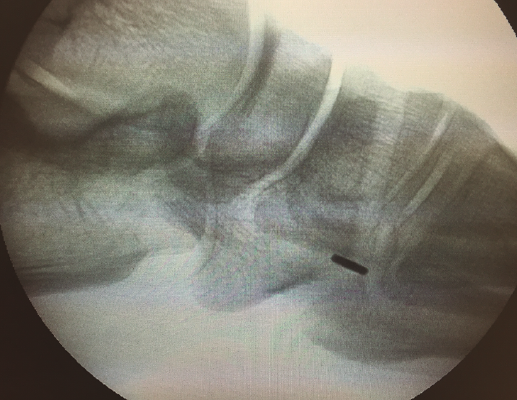

Una vez finalizado este paso, se asegura la estabilidad del sistema mediante la flexoextensión del tobillo (Figura 8) y se comprueba con fotoescopia la correcta colocación de la placa metálica al nivel de la cortical plantar de la cuña medial (Figura 9).

Figura 9. Imagen de fotoescopia para comprobar el correcto posicionamiento de la placa metálica en la superficie plantar de la cuña medial.